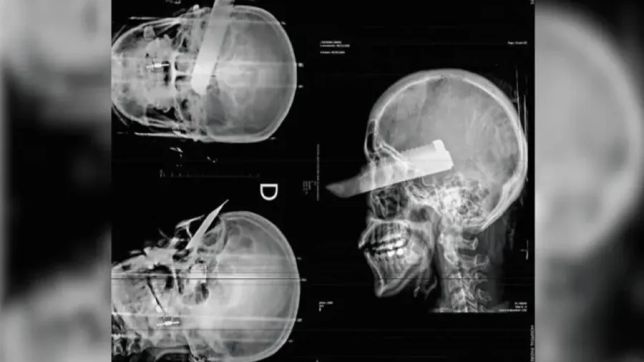

Durante o atendimento, especialistas descobriram que um dos objetos usados pela mãe — uma agulha grossa, normalmente usada para costurar solas de sapato — quebrou-se e deixou uma ponta presa perto da coluna cervical da criança, o que demandou uma cirurgia delicada para remoção do fragmento.

O caso veio à tona quando o menino foi levado ao People’s Hospital of Mojiang County no dia 16 de dezembro, apresentando febre, convulsões e centenas de ferimentos, muitos com crostas escuras indicando lesões repetidas. Médicos estimaram que o bebê tenha recebido entre 500 e 600 picadas de agulha ao longo do tempo.